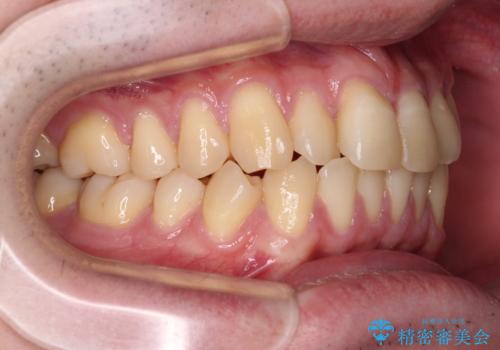

- 前歯のデコボコとクロスバイトを気にして来院された患者様です。

インビザラインでもワイヤー装置でも矯正治療は可能でしたが、煩わしい自己管理なしに短期間で治療を行いたいとのことで、目立たないワイヤー装置にて治療を行うこととしました。

- 1年1ヶ月